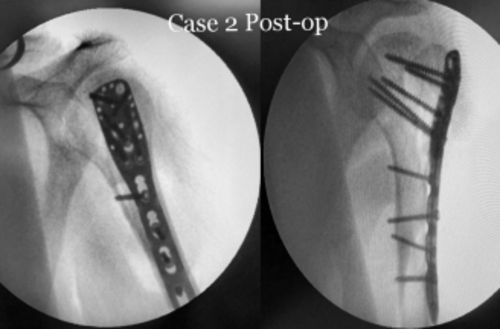

Successful Rehabilitation Following Proximal Humerus Fracture Surgery with Dr. Rahul Jagtap

Patient Mr. R, a 35-year-old male, sought medical attention at our clinic after a motorcycle accident resulted in a fall onto his outstretched arm. Up...